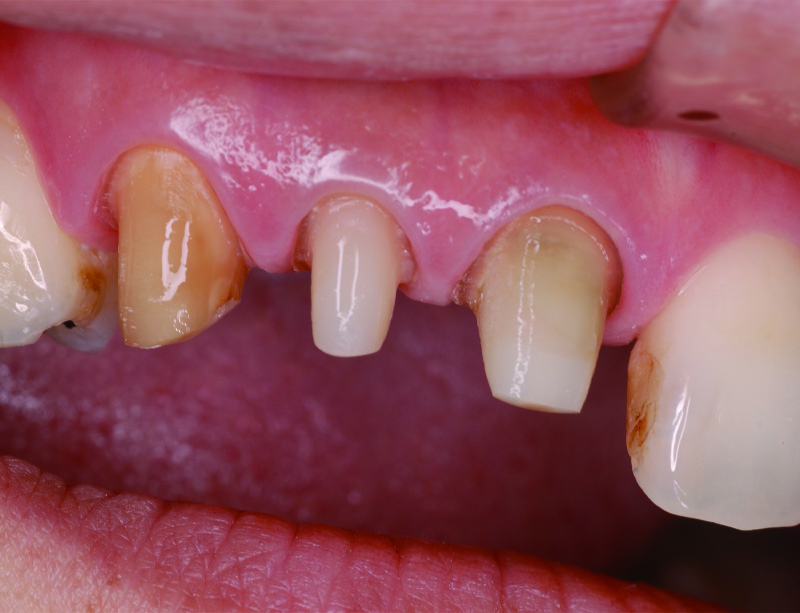

術前の状態です。右上中切歯の被せ物が合っていないことがわかります。また周りの歯の樹脂も劣化が認められます。

被せ物を外すとう蝕が認められました。

土台外すとさらに根管の中にもう蝕が認められました。

残っている歯の量が少ないため、根管治療後に部分矯正にて歯を引っ張り上げる(矯正的挺出)こととしました。

その際は表には仮歯をつけて見た目の確保を行います。

矯正的挺出が終わった状態です。歯とともに歯肉と骨も一緒に引っ張り上げられるので、

手術(歯冠長延長術)によって歯肉と骨を整形し、健康な歯の量を確保します。

歯冠長延長術を行ったところです。

その後土台を築造し、型取りを行います。

右上中切歯にセラミッククラウンを装着して、周りの歯の樹脂もやり替えを行いました。